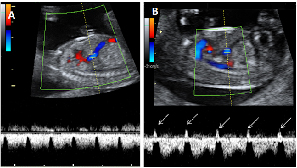

La insuficiencia tricúspide del feto se diagnostica con ecografía Doppler en la semana 12 de gestación. Es un marcador ecográfico de anomalías cromosómicas. Estudia el flujo de sangre que pasa a través de la válvula que une la aurícula derecha con el ventrículo derecho. Cuando da unos valores alterados se recomiendan otras pruebas más invasivas para verificar que el bebé no sufre síndrome de Down.

Doppler pulsado en la válvula tricúspide. Registro normal (imagen A) y registro con insuficiencia (imagen B con flechas).